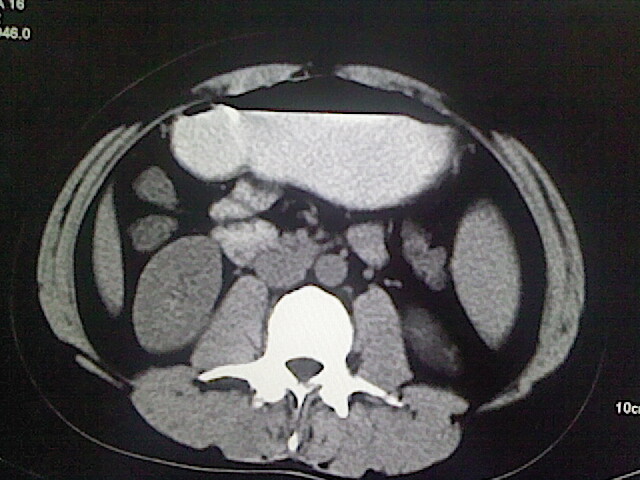

以下是引用卜一在2009-3-14 9:49:00的发言:[br]胆囊萎缩,胆囊壁不规则增厚,内部结构模糊,增强明显强化。另:肝左叶外侧段肝囊肿。支持:慢性胆囊炎!高度可疑:胆囊癌!

以下是引用余辉在2009-3-14 8:48:00的发言:[br]1)慢性胆囊炎。2)肝左叶外侧段肝囊肿。3)脂肪肝。[br]支持,胆囊萎缩,密度增高,不知b超具体有何提示,钙胆汁?结石?

以下是引用jiangjing在2009-3-14 10:18:00的发言:[br]1)慢性胆囊炎。2)肝左叶外侧段肝囊肿。3)脂肪肝。4.】建议行肝功能检查